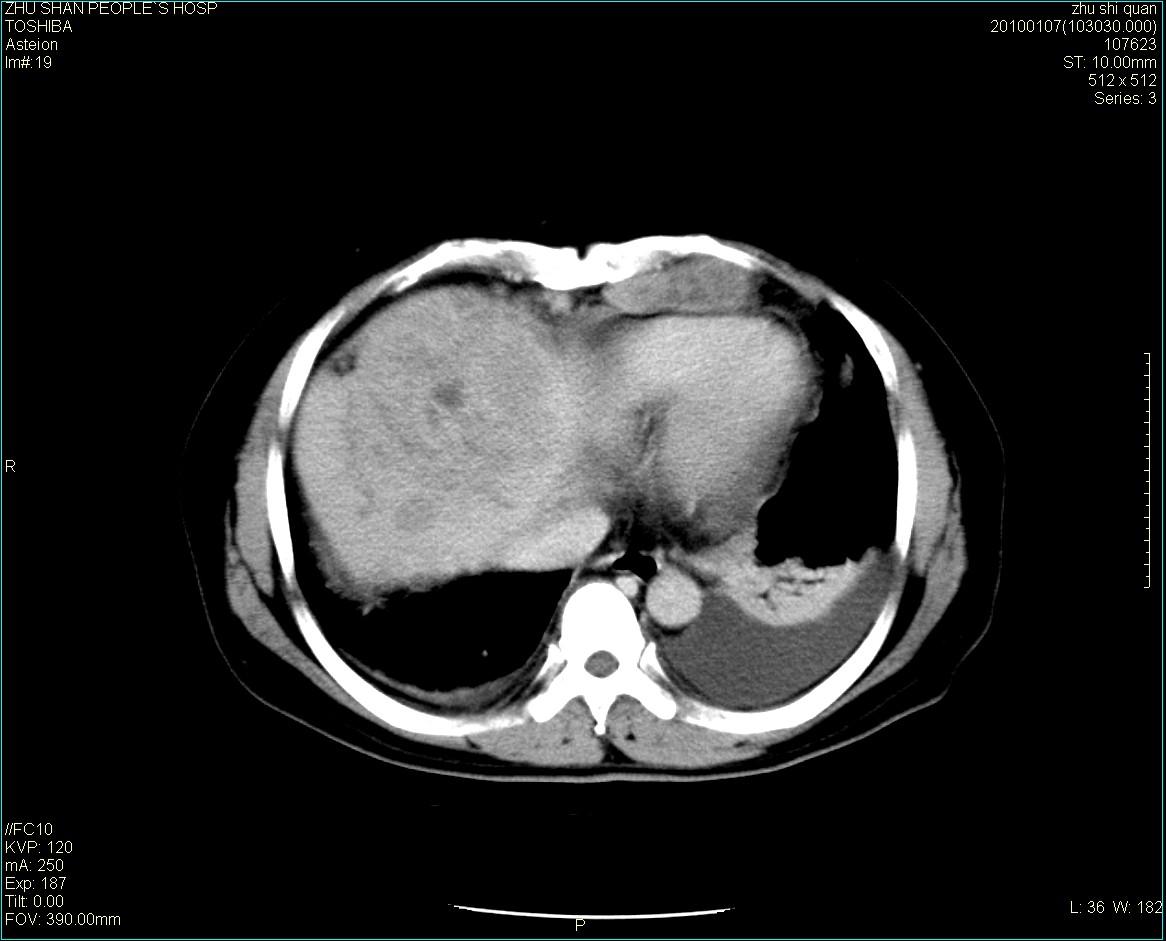

男性病人 肝ca两次术后,今日复查。

1)肝癌并多发性转移。2)双侧胸腔积液(以左侧为甚)伴左下部分肺萎陷。

肝癌术后复发,肝内、脾脏、腹膜后及腹膜多发转移,腹水,双侧胸腔积液(以左侧为甚)伴左下膨胀不全。

肝癌术后复发,肝内、脾脏、腹膜后及腹膜多发淋巴结转移,腹水,双侧胸腔积液。